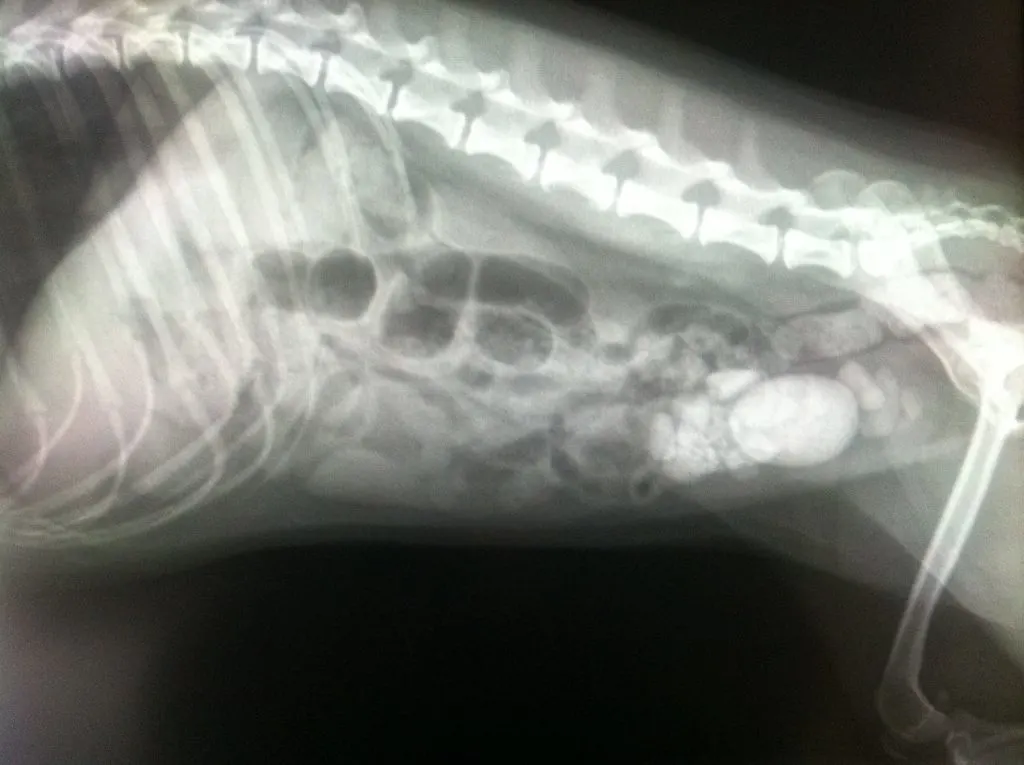

His rock eating seemed to be come ago and over the course of 2 years he would have several x-rays done if we thought he had ingested a fair amount.

I knew the damage the rock eating could do so we did our best to not expose him to any.

When Leroy was 5 1/2 years old, one day on freezing afternoon in the middle winter, he would dig up the foundation of our house and swallowed at least 62 rocks. He puked 1/2 of them up outside my bedroom door in the wee hours of the morning and the following day he would have the remainder of the rocks removed from his stomach.